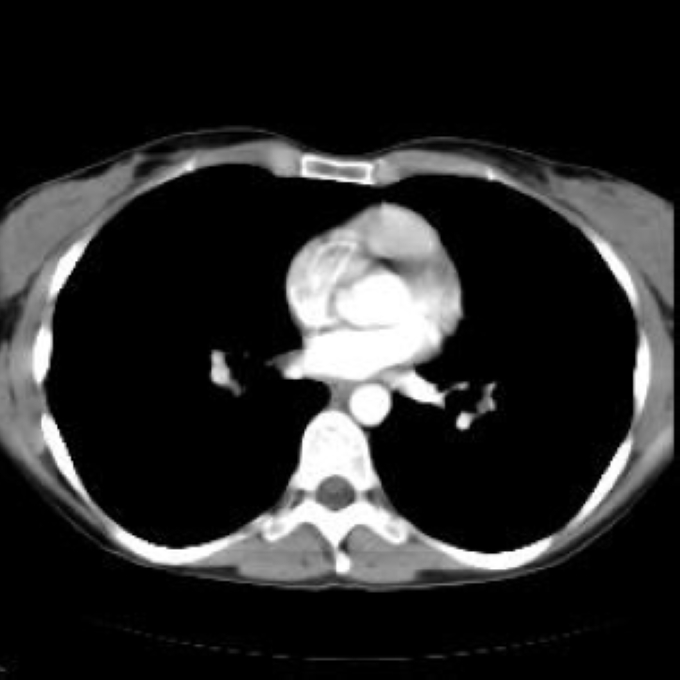

56 year old patient with dyspagia. A tumor of soft tissue was described in upper mediastinum on plain X-ray of the thorax. What is this mass in the upper mediastinum?